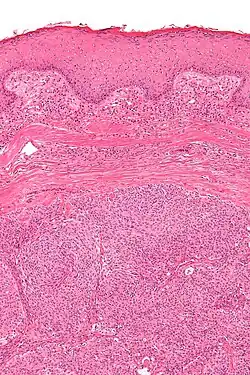

| Micrograph showing an acrospiroma. H&E stain. | |